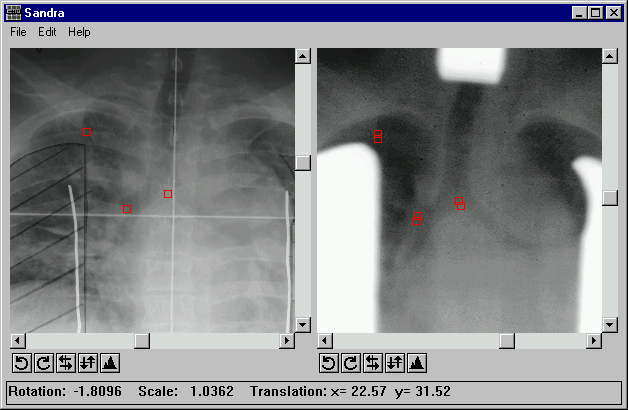

The user interface consists of two scrolled draw widgets placed horizontally next to each other in which the two images to be compared are loaded. Below each scrolled draw widget is a row of buttons to enable the image to be histogram equalized, flipped and rotated in 90 degree increments. A menu bar for the common operations such as loading images, clearing control points, and performing transformations runs along the top of the window. Along the base of the window is a status bar for passing messages to the user. Control points are selected by clicking at the appropriate places in the two scrolled draw widgets (see figure 5).

Pairs of fiducial points are selected by clicking on both images to identify the coordinates in each image of a structure present in it. This causes a small square, the centre of which is the position of the point selected, to be drawn on the image. The points have to be selected in their corresponding pairs, i.e. after the selection of a point in the left image the corresponding point must be chosen in the right image before another point can be selected in the left image. The status bar is used to display the coordinates of the selected fiducial point and how many pairs of points have been selected. The status bar is also used to pass suitable error messages to the user if they click out of sequence on an image.

To provide some feedback to the operator on the accuracy of the selected fiducial points, the points for the transformed image were transformed as well, and plotted alongside those from the reference image. Using this method the better the pairs of points match up in the two images, the closer the two points when plotted. Poorly selected, points are immediately apparent, as they will show significant separation from one another.